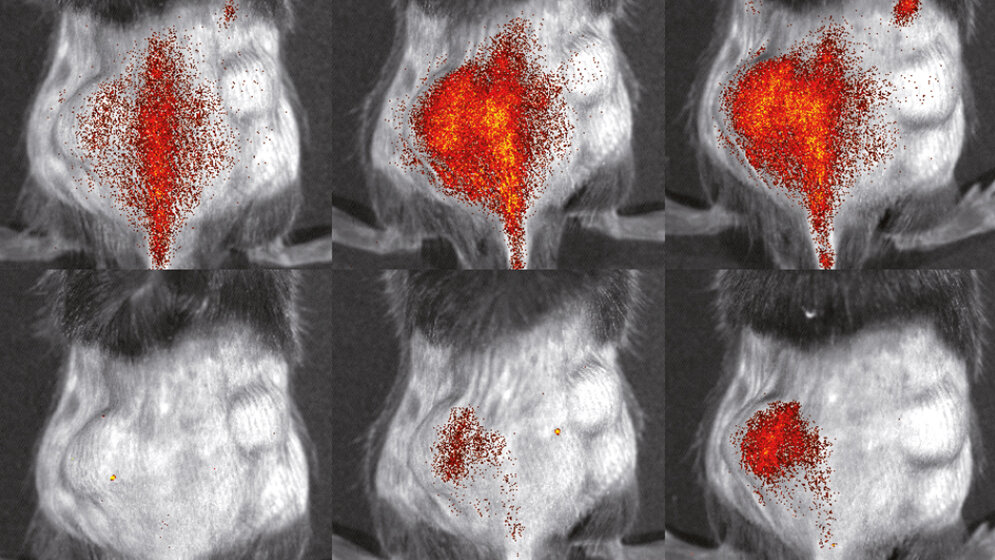

Danach konnten die Bildgebungsspezialisten des Exzellenzclusters die so gewonnenen Zellen mit verschiedenen fluoreszierenden Farbstoffen markieren und sie in lebenden Organismen untersuchen. Sie injizierten Mäusen mit einer entzündungsbedingten Hautkrankheit sowohl mutierte als auch gesunde Immunzellen und konnten so den Weg der Zellen innerhalb desselben Tieres vergleichen. Die Beobachtung fand mithilfe der Fluoreszenz-Reflektions-Bildgebung statt. „Wir konnten sehr genau beobachten, wie unterschiedlich sich die verschiedenen Immunzellen verhielten. Zum Entzündungsherd schafften es etwa doppelt so viele gesunde Immunzellen im Vergleich zu den genetisch veränderten“, sagt Dr. Lisa Honold, ebenfalls federführende Autorin der Studie.